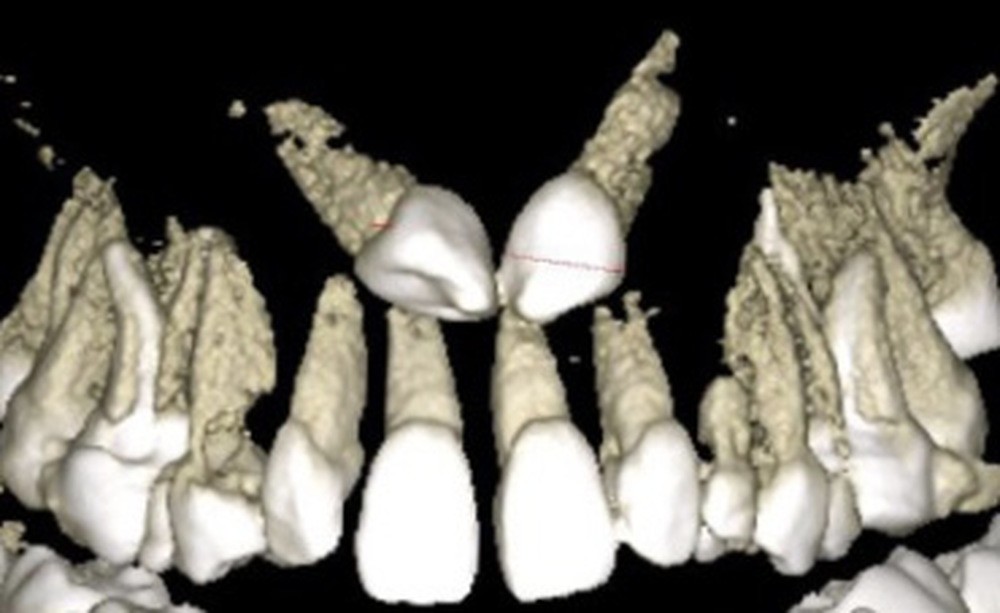

L’examen radiologique 2D nous confirme l’inclusion de 13 et 23 en position haute, oblique en bas et en avant, couronnes en projection des apex de 11 et 21 et nous permet de quantifier le décalage squelettique (fig. 3 et 4). L‘examen radiologique 3D (cone beam) objective les rapports…